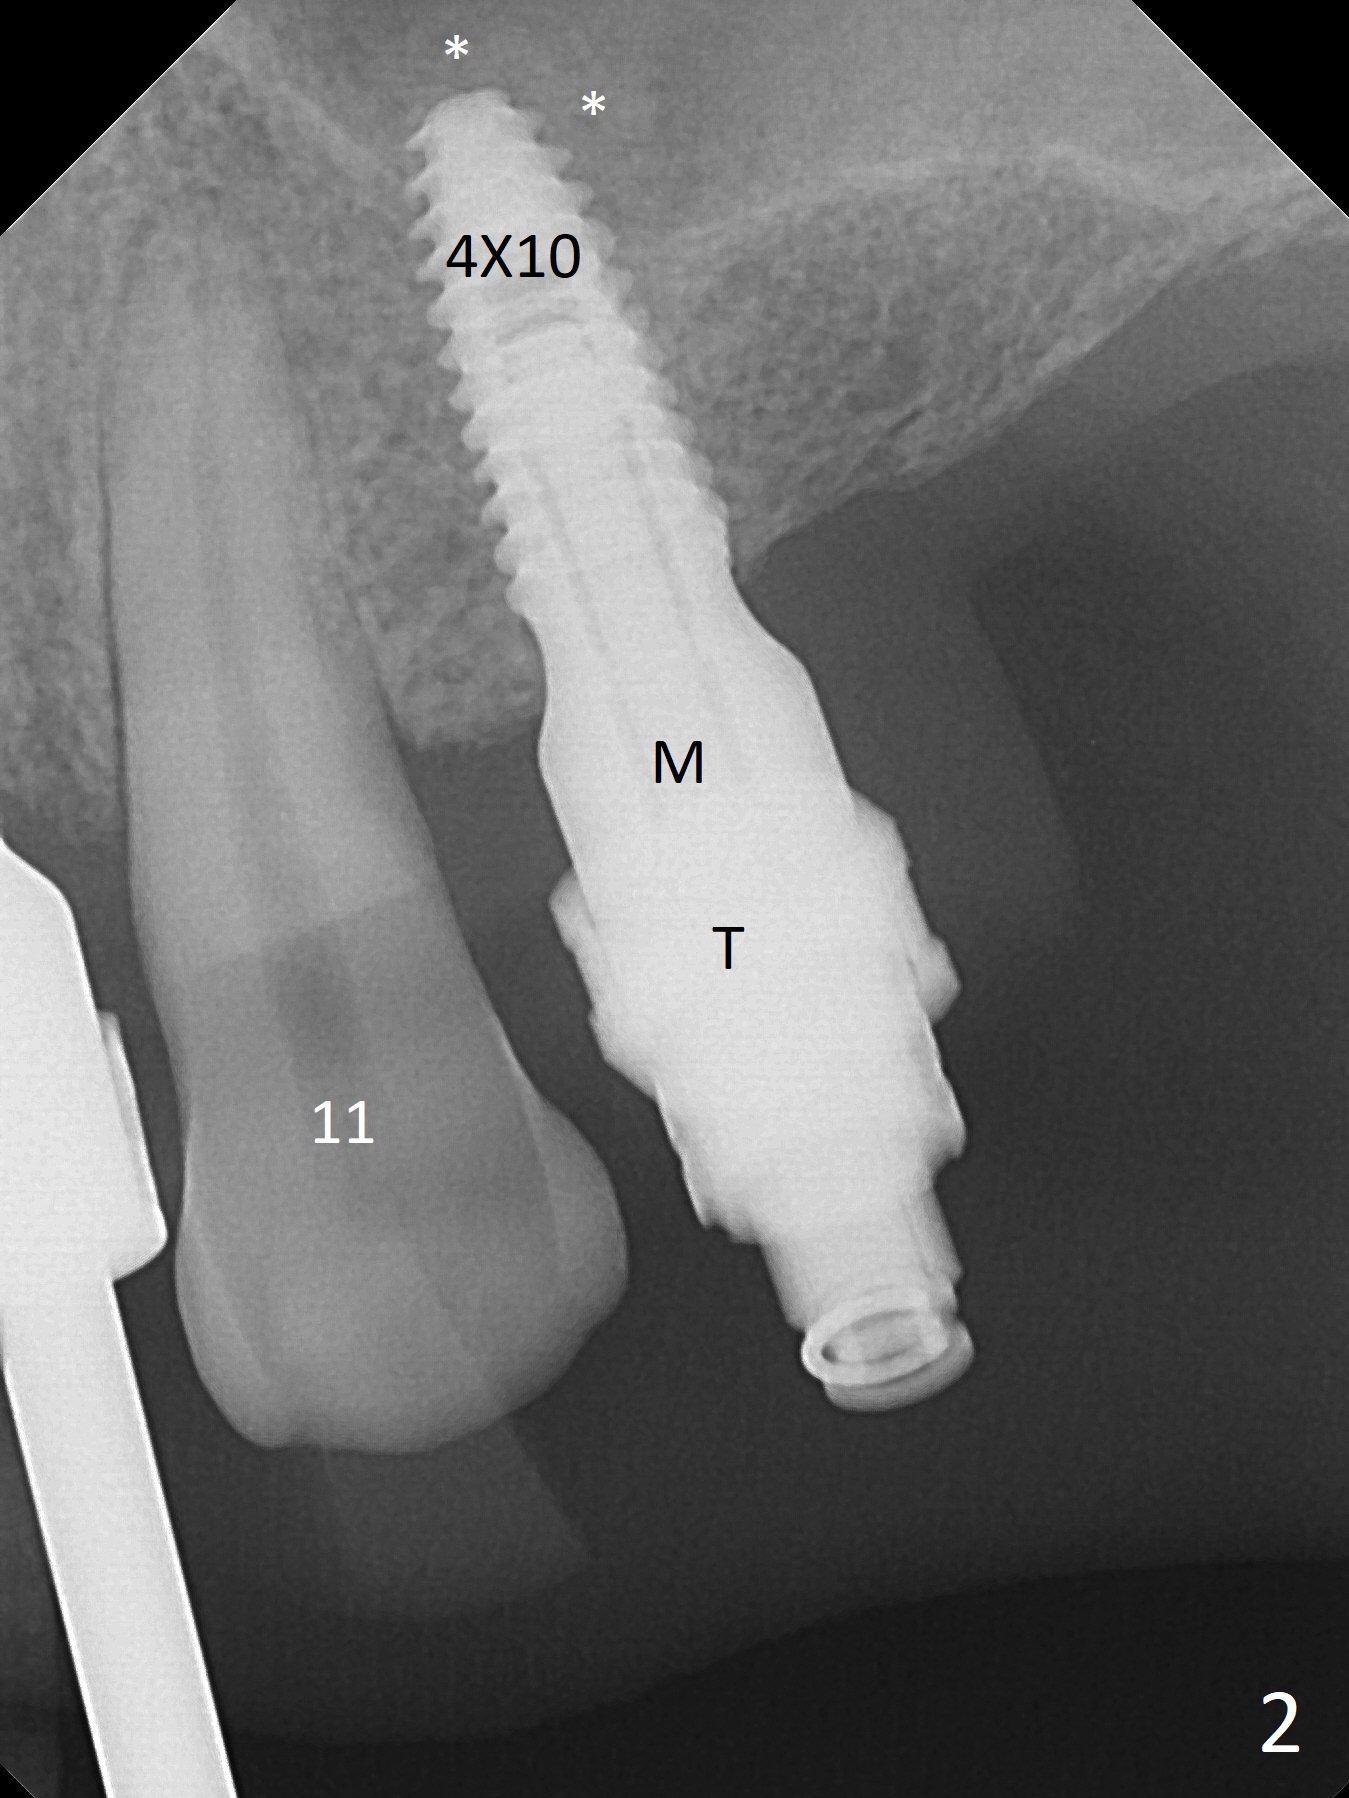

After a 4x10 mm implant is placed with fixture mounting (Fig.2 M) following sinus lift (*) at #12, osteotomy is initiated at #10 (Fig.1 (T: tube of surgical guide)). It appears that the drill (D) has good trajectory (between the Incisive Canal (red dashed line) and the canine root). The final position of the implant at #10 is acceptable (Fig.3). The implant at #12 is placed deeper (Fig.4 (arrow), as compared to Fig.2) because of clinically buccal superficial placement. The most critical challenge is anterior deep bite associated with posterior collapse. Periodontal dressing is applied. When the latter dislodges, there is minimal clearance for a provisional. Periodontal dressing is re-applied. The patient (smoker, partial edentulism with occlusal interference) returns for provisional nearly 1 month postop with chief complaint "something is lost in the back". In fact the healing abutment at #12 is lost with buccal granulation tissue (Fig.5). When a new abutment is seated, there is discomfort. When a healing screw is placed, it cannot be seated completely with two separate trials (Fig.6,7). Should we leave it as it is or open up for complete seating? It appears that the implant is loose. After preparation for clearance at #10, the abutment is retightened. It appears to turn with the underlying implant with discomfort. A 4x5 mm healing abutment is placed to reduce micro-movement. One week later, the infection at #12 dissolves with oral Amoxicillin (Fig.8). Due to limited occlusal clearance and implant tenderness when the abutment abutment is retightened, the cemented abutment is changed to a healing abutment. The implant at #10 seems to be osteointegrated, while the healing screw at #12 remains incomplete seating 3 months postop (Fig.9). The loose healing screw cannot be retightened securely, as there is bone loss around the implant 3 months postop (Fig.10 *). When a 4.5 mm x 15 degree 4 mm cuff angled abutment is placed, the mesiodistal trajectory improves (Fig.11), but there is no occlusal clearance (Fig.12). The latter would form when posterior support is established (Fig.13, either removable appliance (which the patient hates) or fixed one (finance)). Fig.14 shows the unhealed site of #12. Incision confirms the bone loss around the implant, which is removed. Although the sinus floor is absent, there is no membrane perforation. After debridement, allograft mixed with small amount of Osteogen is placed (Fig.15,16 G) and covered with Osteogen plug and 6-month membrane.